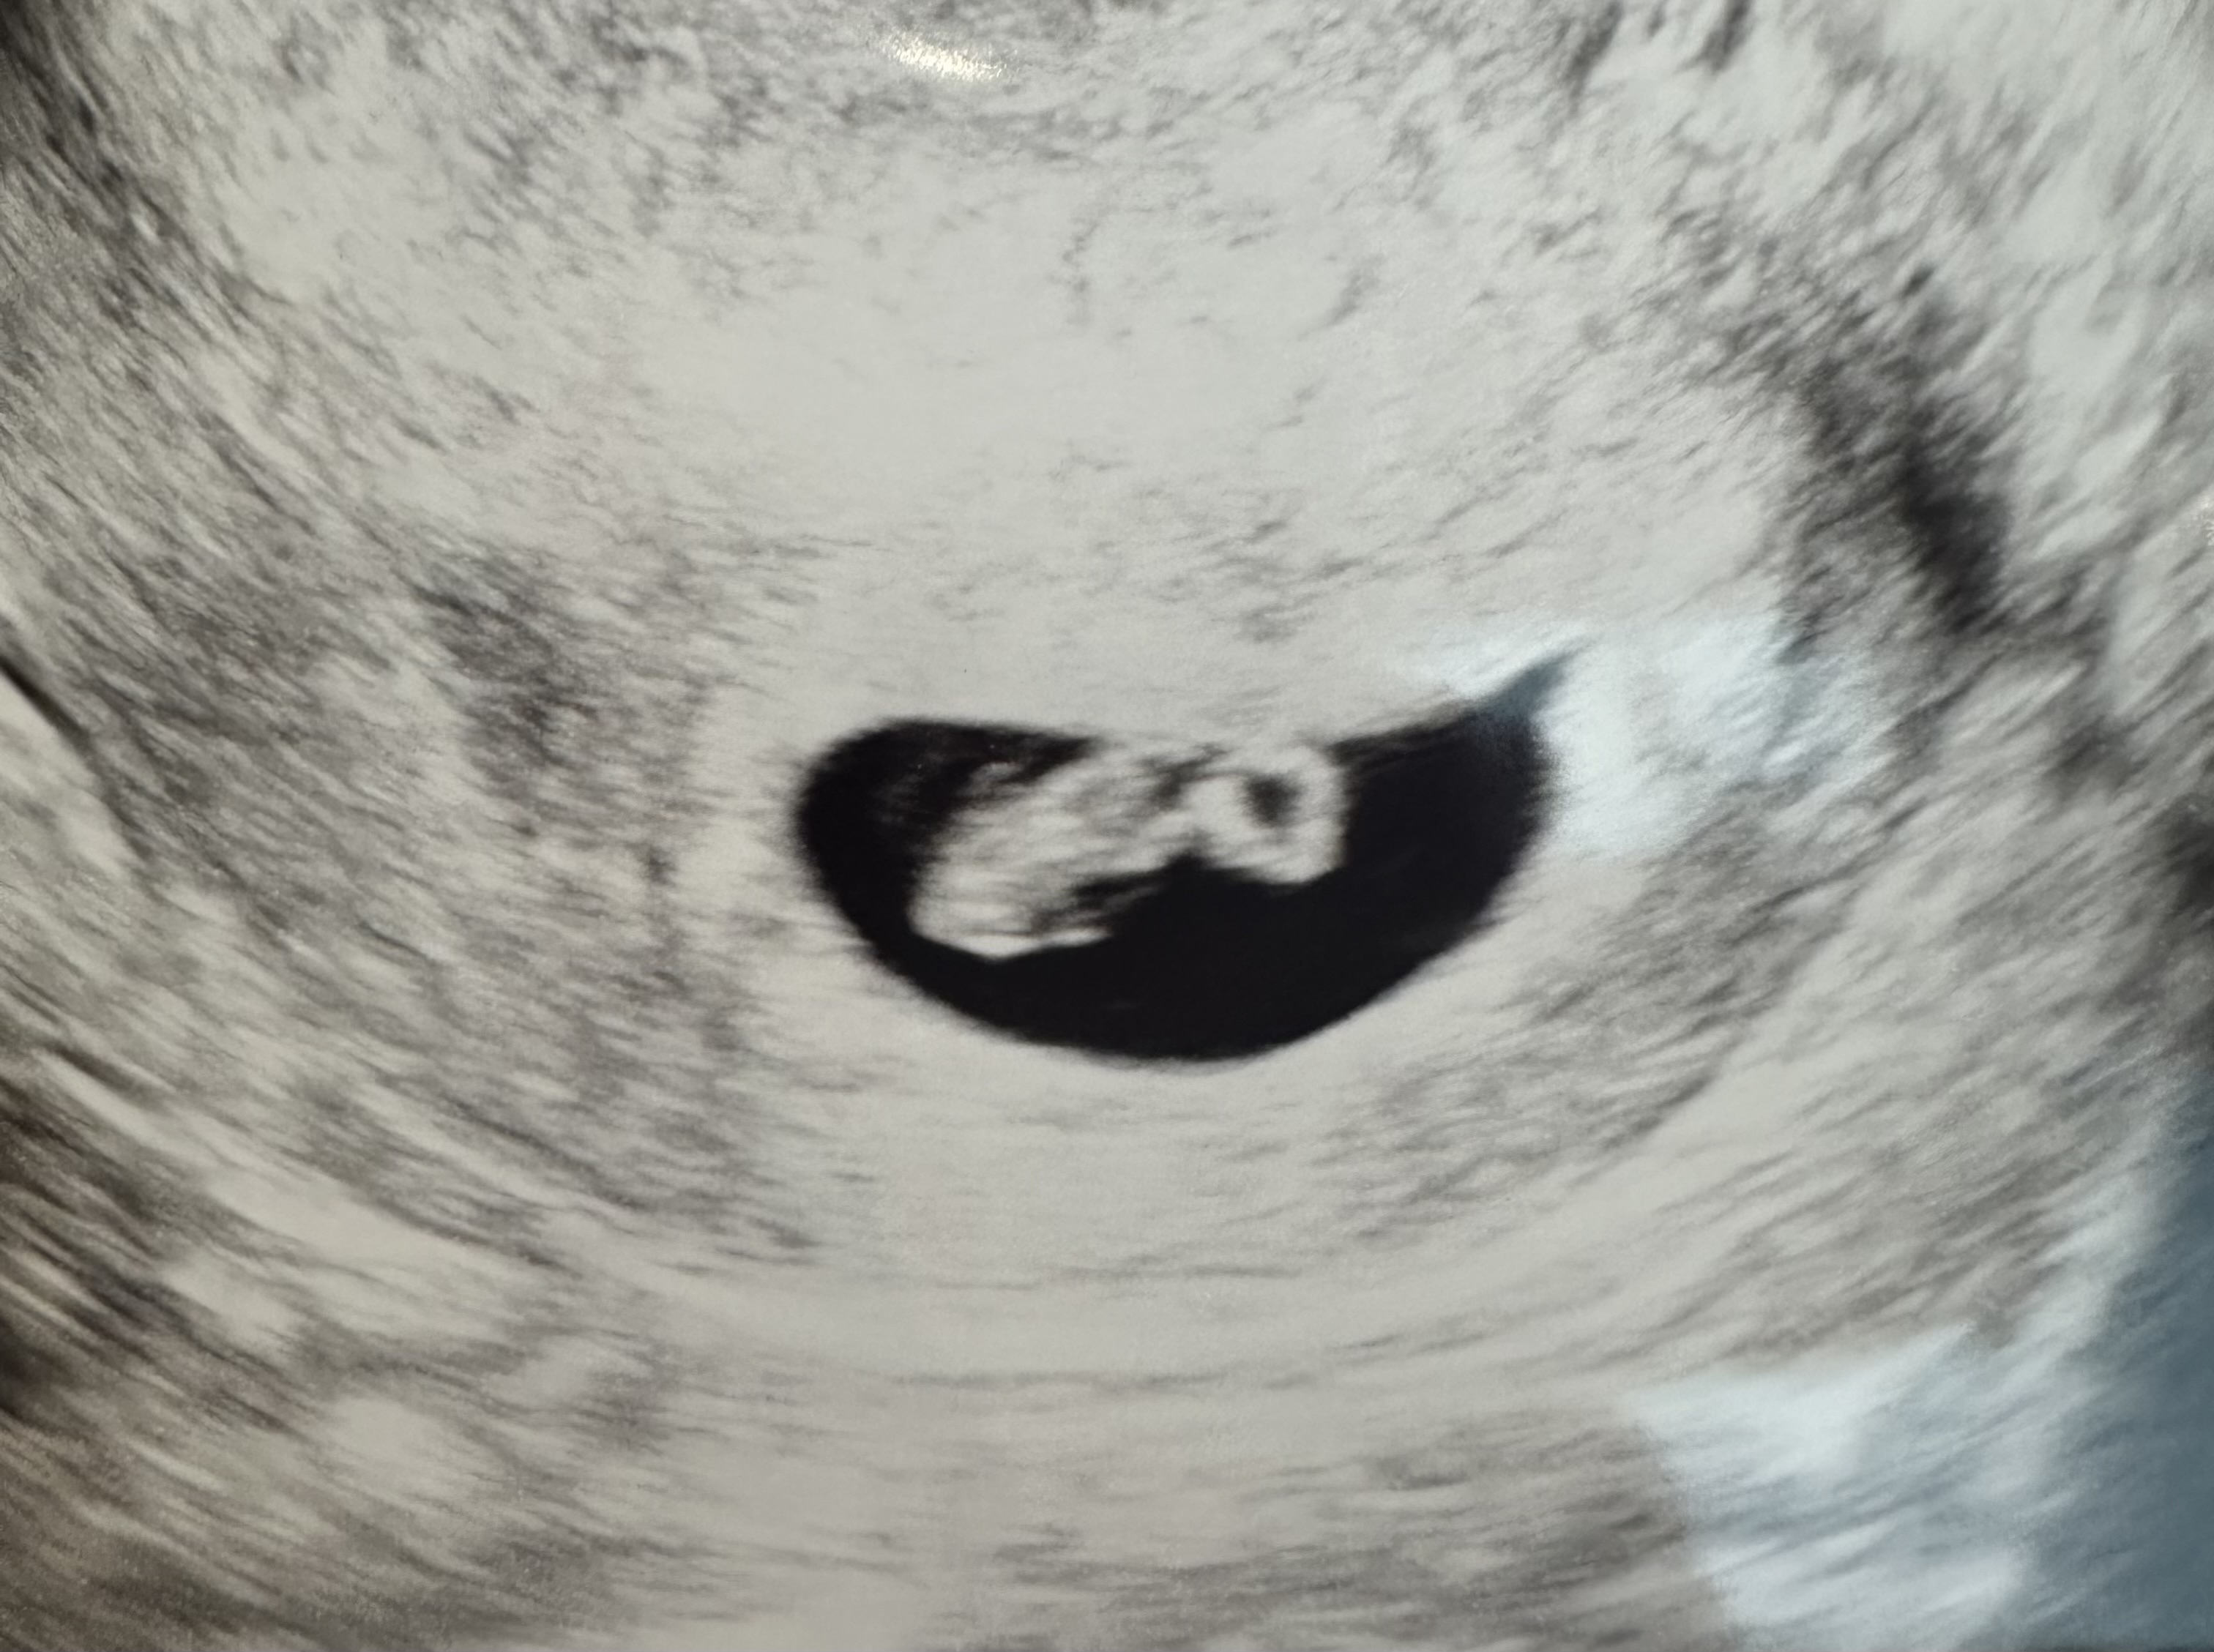

| 가슴 떨리는 임신 이야기를 공유해 주세요. | 결혼 후 아이를 너무 좋아해 바로 임신을 시도했지만, 매번 임신테스트기에는 단 한 줄만 보였습니다. 그렇게 1년이 흘렀고, 서울IVF여성의원을 추천받아 인공수정 2차 후 본격적으로 시험관 시술을 시작하게 되었습니다. 세 번째 시험관 이식에서는 임신 증상이 전혀 없어서 큰 기대조차 하지 않았습니다. 그런데 이식 후 7일째 되는 날, 피비침이 있어 “이번에도 안 됐구나”라고 생각하며 병원에 생리 시작 사실을 알렸습니다. 하지만 이유정 원장님께서는 아직 피검사 전이니 끝까지 지켜보자며, 착상혈일 수도 있다고 말씀해주셨습니다. 그날 저녁, 혹시나 하는 마음에 임신테스트기를 해보았고, 난생처음 두 줄을 확인했습니다. 그 순간의 벅찬 감동은 아직도 잊지 못합니다. |